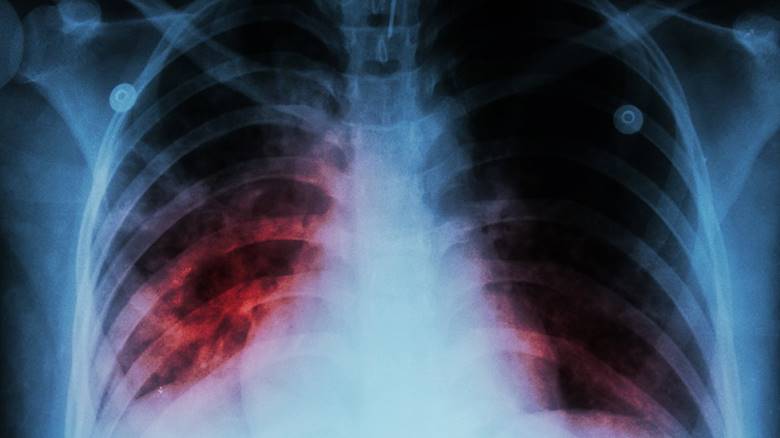

4. Lao phổi

Bệnh lao đã và đang là một đại dịch trên toàn thế giới, ước tính cứ sau 25 giây nó sẽ cướp đi 1 sinh mạng. Theo Tổ chức Y tế Thế giới (WHO), mỗi năm có 1,3 triệu người chết vì căn bệnh này. Đây là một bệnh truyền nhiễm, tấn công hệ hô hấp và các cơ quan khác và phá hủy các mô cơ thể.

Nó thường lây truyền qua đường hô hấp khi người bệnh ho hoặc hắt hơi. Nó thường xảy ra ở các nước thế giới thứ ba như Châu Phi, Châu Á và đặc biệt tàn phá ở các khu vực trên thế giới có HIV / AIDS, vì nó thường gây tử vong ở những người mắc bệnh suy giảm miễn dịch này.